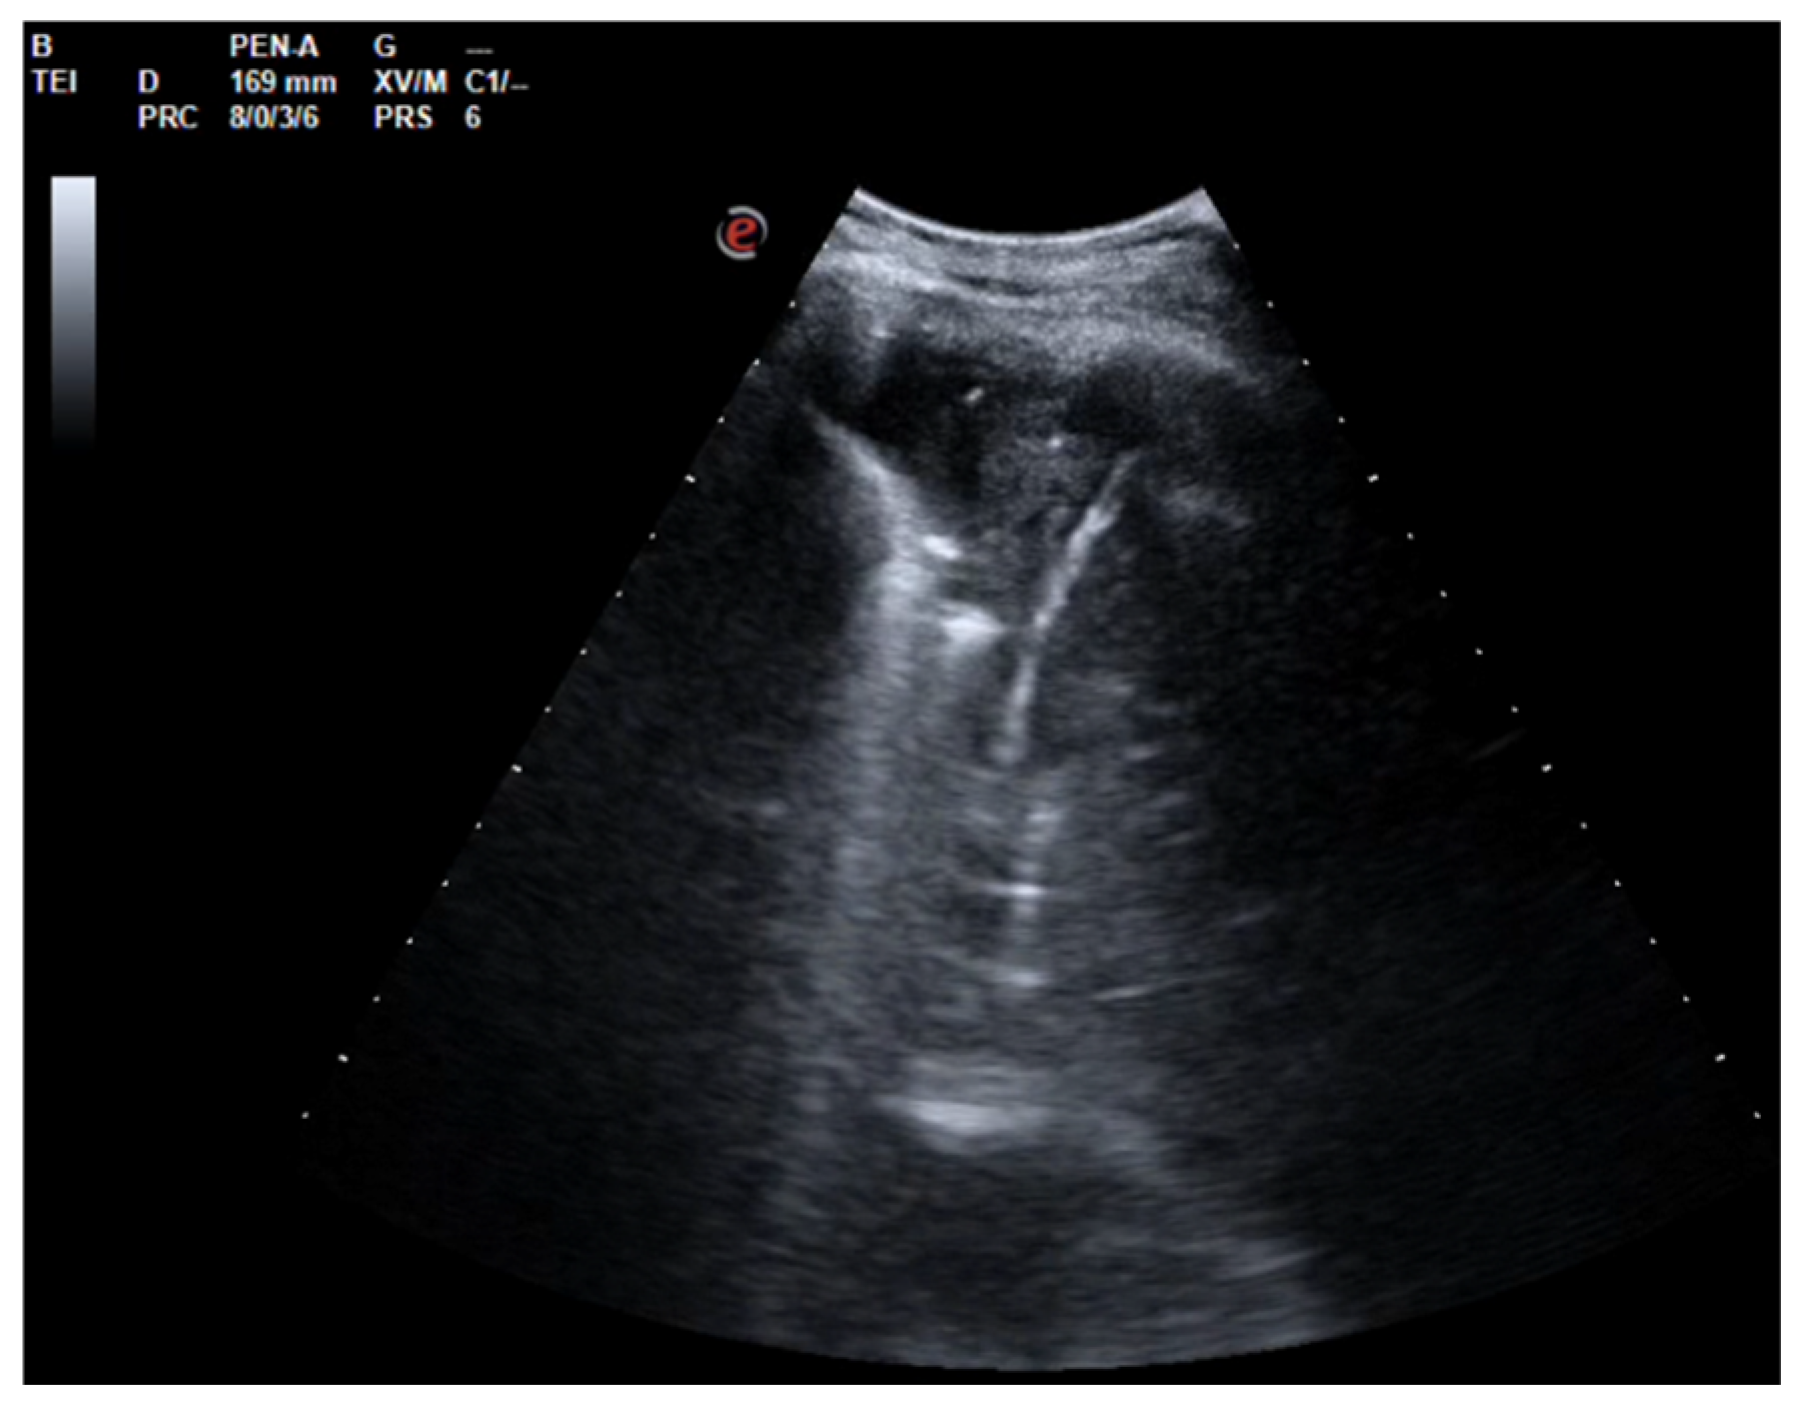

A 26-year-old man was admitted to our hospital for worsening dyspnea at rest and pain in the right hemithorax. The patient complained of a fever (39.5 °C) and productive cough for about 1 week, with mild hemoptysis in the days prior. His medical history included bilateral bronchiectasis and bronchial asthma, for which he received inhalation therapy with a long-acting antimuscarinic agent, long-acting bronchodilator, and inhaled corticosteroid. He had no family history of respiratory disease and had been tested for cystic fibrosis transmembrane regulator (CFTR) gene mutations, with negative results. The patient did not smoke cigarettes, drink alcohol, or use recreational drugs. An arterial blood gas (ABG) analysis showed acute hypoxemic normocapnic respiratory failure; therefore, oxygen therapy with a 28% FiO2 via a Venturi mask was administered. Chest radiography showed an area of opacification at the right base. Empiric antibiotic therapy with 12 mg/kg teicoplanine (Q8H) and 4.5 g piperacillin/tazobactam (Q6H) was then started on suspicion of community-acquired pneumonia. Blood tests upon his admission showed leukocytosis (WBC 18.84 × 109 cells/L) with predominant neutrophils (14.5 × 109 cells/L). Legionella and pneumococcal antigens in his urine were negative. Blood cultures after 72 h were negative. Chest ultrasonography revealed a multiloculated effusion (Figure 1).

After the placement of a chest tube, pleural fluid samples were sent for microbiological and physicochemical analysis, which confirmed the diagnosis of pleural empyema. Two days after the placement of the chest tube, the fluid flow decreased. To break up the fibrin pockets present in the empyema and promote the complete evacuation of the fluid, irrigation of the pleural cavity with 200,000 UI of urokinase in 50 mL of saline solution was performed under US guidance (Figure 2).

Figure 1. Chest US at admission. Multiloculated pleural effusion.